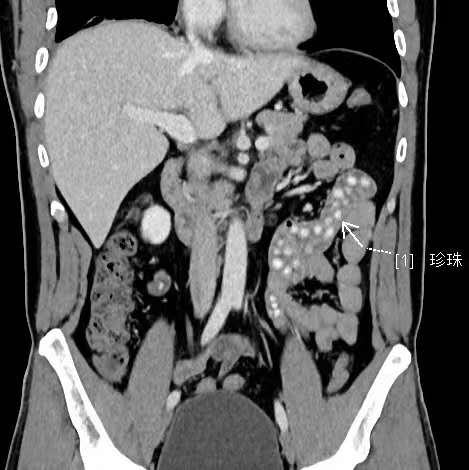

拍出來(lái)的片子讓醫(yī)生大吃一驚,小林的胃腸道里布滿了高密度陰影。仔細(xì)一看,醫(yī)生發(fā)現(xiàn)是一顆顆沒(méi)有消化的東西,像珍珠奶茶里面的“珍珠”。

“密密麻麻,粗略估計(jì)有幾十顆。”影像科副主任醫(yī)師薛貞龍告訴現(xiàn)代快報(bào)記者,奶茶里的珍珠很難消化,CT顯示腸腔內(nèi)圓形結(jié)節(jié)狀高度密影。他提醒,對(duì)于炎性腸病患者,尤其是伴有輕中度腸道狹窄的患者,最好別喝奶茶,很容易誘發(fā)腸梗阻。